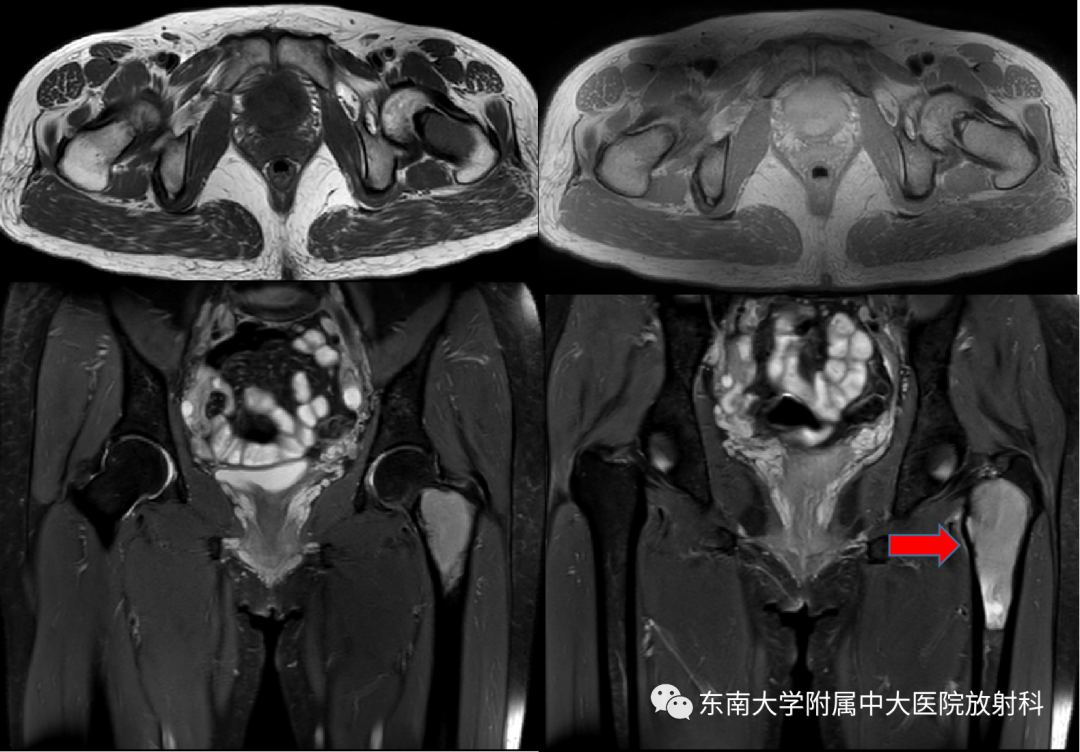

病例

•女,46岁

•主诉:左侧腹股沟区疼痛2月余

•现病史:患者2月余前无明显诱因左侧腹股沟区出现疼痛,呈持续性酸胀痛,休息后缓解,偶有感觉异常